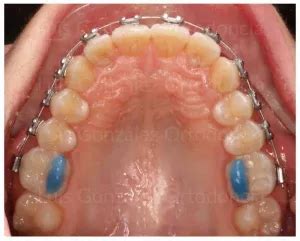

- Región anterior: Levante efectuado en las caras palatinas de los incisivos centrales superiores.

- Región posterior: Levante realizado en la cara oclusal de los molares y premolares.

El composite es el material más comúnmente utilizado. Este material es conocido por su durabilidad y fácil manipulación. Se emplea para crear tanto levantes de mordida prefabricados como personalizados.

Otra opción popular es la resina fotopolimerizable. Este material se usa particularmente en levantes posteriores y tiene la ventaja de liberar flúor, lo que brinda protección adicional a los dientes.

Los mini moldes de composite permiten una aplicación rápida y precisa, especialmente útil en la región anterior.